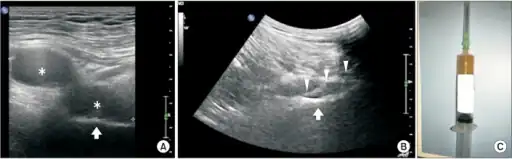

Pudendal nerve entrapment syndrome due to a Ganglion cyst-a) Ultrasound image showed a bilobed cystic mass b) image guides a 16-gauge spinal needle to ganglion cystic mass for aspiration c) 4 mL of thick mucoid material was aspirated